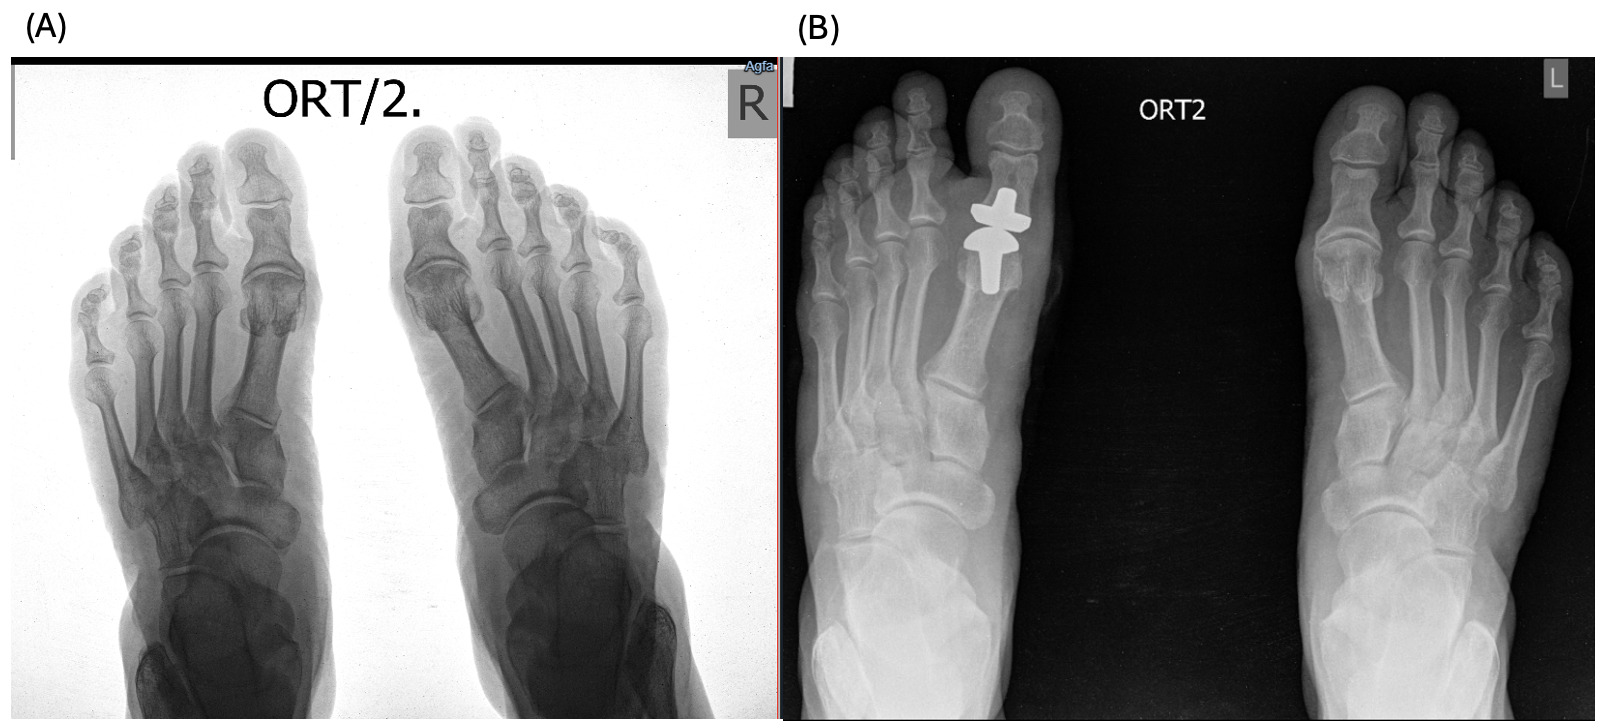

A 61-year-old female patient with a history of trauma on the left first MTP presented to the clinic with complaints of pain and limited range of motion of the right foot first MTP for the last several years. The patient was receiving conservative treatment within the last year with temporary relief; therefore, the surgical intervention was recommended and the patient was referred to our clinic. Physical examination revealed almost no movement and pain on palpation, as it can be seen on Figure 1 (A).

After the total first MTP replacement using ceramic implant, 2 and 6 months later, there is preserved improvement in the joint mobility, absence of pain and discomfort during movement (Figure 1 (B, C)). The patient reports satisfaction with the use of joints.